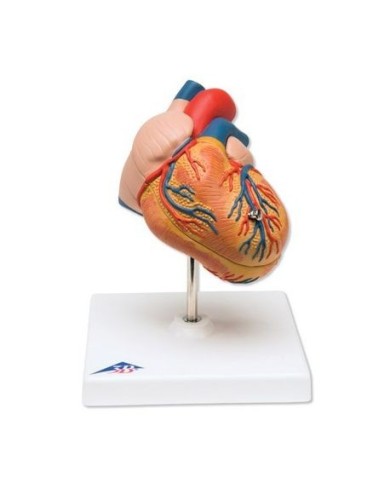

Su base removibile

Modello anatomico di cuore, ingrandito 2 volte, su cavalletto

Questo modello dettagliato mostra, oltre alle strutture anatomiche del cuore, anche una parte del diaframma (base)